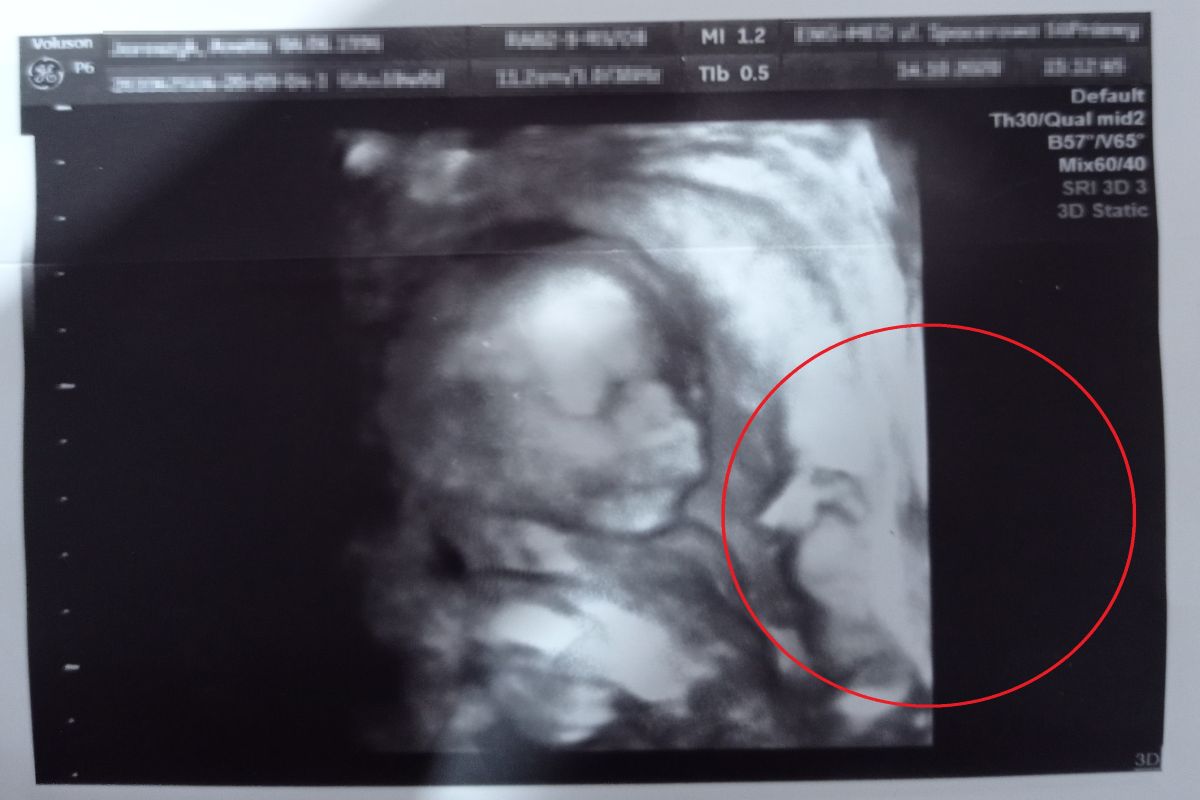

Czytelniczka o2.pl podzieliła się z redakcją swoim zdjęciem z USG ciąży. Powód? Gdy przyjrzała się fotografii uważnie, okazało się, że widnieje na nim nie tylko twarz jeszcze nienarodzonego dziecka. Czy to mógł być anioł stróż?

Jak relacjonowała pani Aneta, nadesłane zdjęcie z USG przedstawia jej synka. Chłopiec przyszedł na świat zaledwie kilka miesięcy temu, bo 21 marca, o godzinie 21:00.

Jak wyznała pani Aneta, wierzy, że jej samej w trakcie ciąży przytrafiła się podobna historia, co bohaterce artykułu. Zdjęcie na którym – według czytelniczki o2.pl – widać anioła stróża malucha, zostało wykonane w połowie października ubiegłego roku.

Na zdjęciu USG wyraźnie widać... dwie twarze. Jednak przyszła mama wcale nie spodziewała się bliźniąt

Chciałam się podzielić naszym zdjęcie, ponieważ był to dla nas szok – nasz synek, który się urodził w tym roku 21 marca o 21, też ma anioła stróża na USG – relacjonowała pani Aneta w rozmowie z o2.pl.

Trudno jednoznacznie rozstrzygnąć, w jaki sposób na zdjęciu z USG pojawiła się przypominająca ducha postać. Osoby sceptycznie tłumaczą taką obecność złudzeniem optycznym, a wierzące – uważają, że to znak, że jeszcze przed narodzinami nad dzieckiem czuwa anioł stróż.